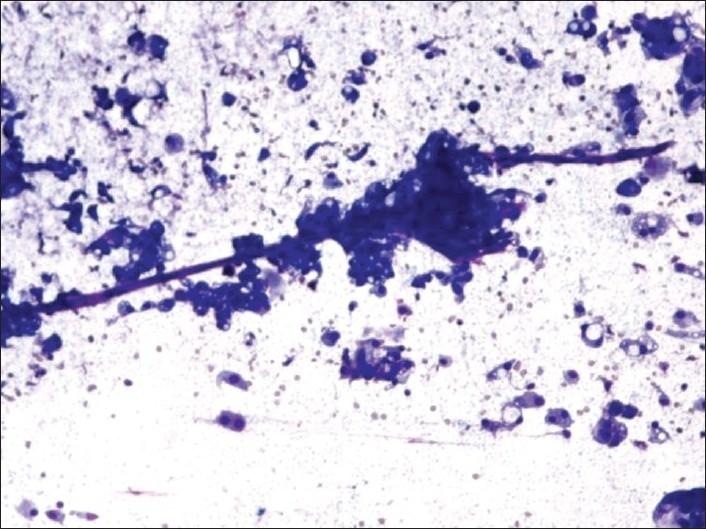

Secretions were seen in 16 of 160 breast carcinomas. Eleven were invasive ductal carcinoma (IDC), three were mucinous and two were secretory carcinomas. In IDC, minimal intracytoplasmic secretions were seen in 10, nuclear grades of 2 and 3 in 9, cell clusters with irregular margins in 6, and necrosis in 4. All mucinous and secretory carcinomas were nuclear grade 1. Extensive extracellular secretions and cell clusters with rounded contours were seen in mucinous carcinomas. In secretory carcinomas, the secretions were predominantly intracellular; stringy vasculature was a unique feature.

160例乳腺癌中有16例可见分泌物。11例为浸润性导管癌(IDC),3例为黏液癌,2例为分泌性癌。在IDC中,10例可见少量胞质内分泌物,9例核分级为2级和3级,6例细胞簇边缘不规则,4例有坏死。所有黏液癌和分泌性癌核分级均为1级。黏液癌可见大量细胞外分泌物和轮廓圆形的细胞簇。在分泌性癌中,分泌物主要为细胞内的;条索状脉管系统是其独特特征。